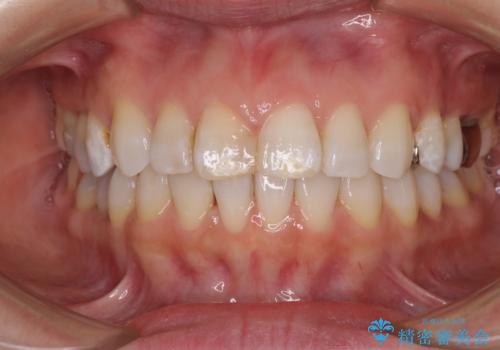

先天欠損のある歯列 インビザライン矯正

- 上顎前歯の突出感を気にして来院された患者様です。

下顎前歯2本が先天欠損しており、上顎歯列に対して、下顎歯列がアンバランスに小さい状況でした。

左右上顎側切歯2本が矮小歯であるため、上顎の抜歯ではなく、IPR(歯と歯の間を削る)と歯列全体の後方移動によってバランスを整えることとしました。

目立ちにくい装置を希望されたため、インビザラインにて治療を行うこととしました。